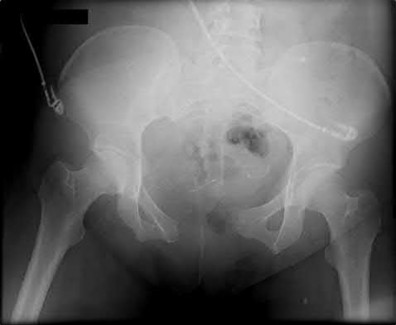

2. # A 35-year-old woman is involved in a head-on collision while driving. Initial radiographs are shown in Figures 8a and 8b. Injury to what vessel increases the risk for osteonecrosis of the injured bone?

1. Dorsalis pedis artery

2. Perforating peroneal artery

3. Lateral tarsal artery

4. Artery of the tarsal canal

5. Artery of the tarsal sinus Corrent answer: 4

The patient has a Hawkins type III talar neck fracture-dislocation with a risk of osteonecrosis ranging from 69% to 100%. Anatomic studies have shown that the artery of the tarsal canal supplies the lateral two thirds of the talar body.

The other vessels listed provide no significant contribution to the talus.